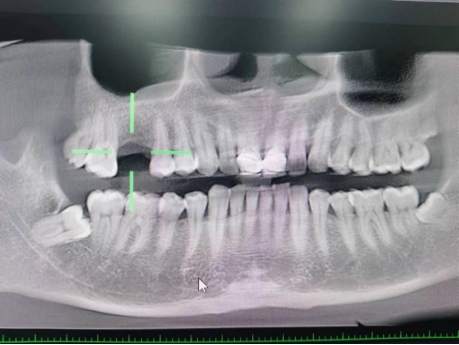

武先生术前检查图

据了解,53岁的武先生,因右上后牙缺失多年,缺失的牙齿给他造成了不小的烦恼,影响到了正常咀嚼功能。在了解到小艾电竞 口腔科能开展种植牙手术以后,武先生前来咨询,经过仔细全面的口腔检查和CT检查、检验等检查,武先生符合种植牙条件,决定实施右上后牙区种植牙的修复方案。本次手术由陈河林博士主刀,黄魁副主任做助手,在口腔中心成功完成该院首例种植牙手术,手术历时约30分钟,术中微创操作,患者全程无痛,术后无不良反应,整个诊疗过程舒适、安全、精准,经术后CT检查种植体位置精确。